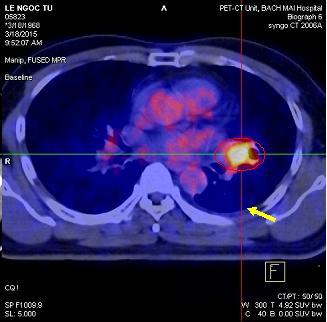

Ngày 28 tháng 10 năm 2014, bệnh nhân được chụp PET/CT cho thấy: Thùy trên phổi trái có khối tăng hấp thu F-18 FDG, kích thước 4,3x4,1x4,2cm, max SUV=8,9. Dịch màng phổi trái 0,7cm không tăng hấp thu F-18 FDG.

Hình 3. Hình ảnh chụp PET/CT: khối u phổi trái tăng hấp thu F-18 FDG kích thước 4,3x4,1x4,2cm (vòng tròn đỏ), tràn dịch màng phổi trái (mũi tên vàng, đã chọc tháo dịch màng phổi trái trước đó)